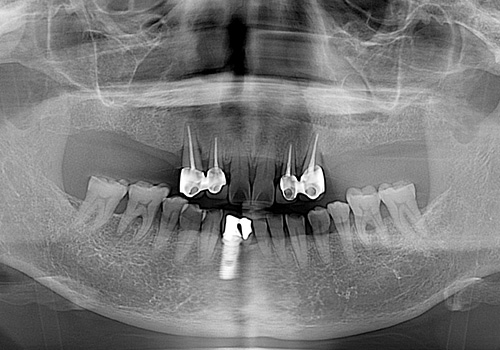

김○근님 임플란트 식립 후

2023년 6월 -